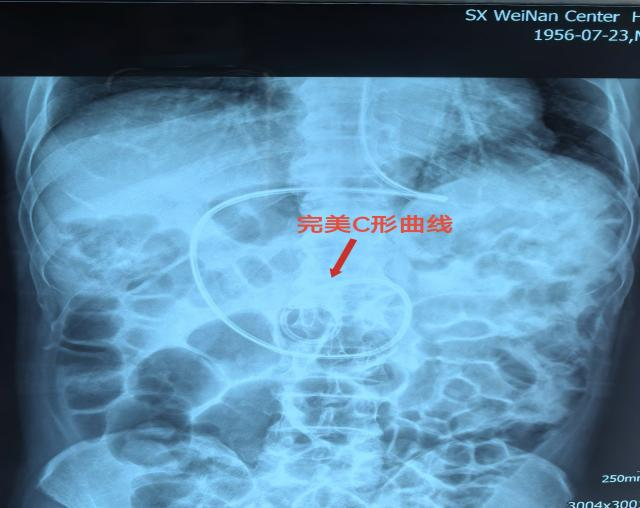

为尽快解决患者的营养问题,避免因误吸反流引起的并发症导致病情加重,护士长杨霏与护士程张雅、杜京经过精准评估,决定对患者进行幽门后喂养。通过徒手盲插,成功在床旁置入空肠营养管,并经DR验证,确认空肠管已完美到达指定位置,形成理想的“C”型曲线。